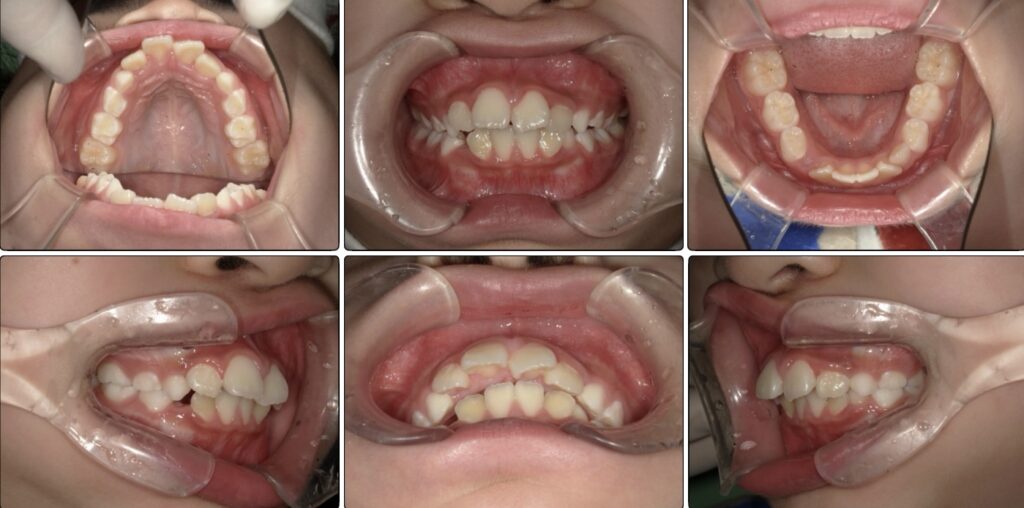

治療開始時

現在

口が開いていることが多く、閉じようとするとこのように下唇を噛んでしまうことも多かったです。

飲み込みの時にはかなり口唇に力を入れていて、下顎が後退し上顎はV字歯列になっていました。

普段から口を閉じる意識も頑張ってくれていて呼吸のアクティビティが終わる頃には(治療開始から6ヶ月後)

にはアクティビティとマウスピースの装着のみで下の歯のがたつきが少なくなり上顎もV字歯列が改善されていました♪

半年でここまで変化が現れるのはしっかりとアクティビティ、マウオブレースの装着、日々の意識が習慣化されている証拠でもあります!!